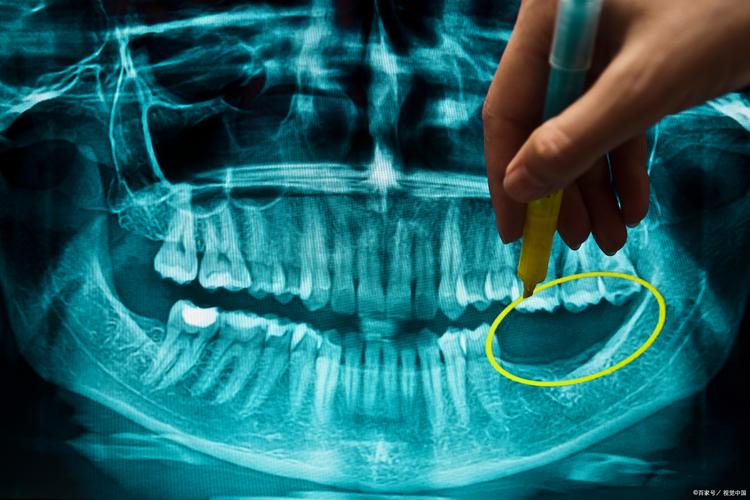

- 颌面部外伤: 评估颌骨骨折(下颌骨、颧骨、上颌骨)、牙齿损伤(牙根折断、脱位)、异物定位。

- 颌骨囊肿、肿瘤及瘤样病变: 精确定位、评估范围、与重要结构关系。

- 复杂牙髓病和根尖周病: 评估复杂根管形态、根管内器械折断、根尖周病变范围。